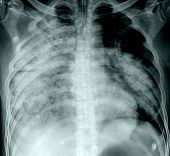

Strep Pneumonia In Older Adults

Strep Pneumonia In Older Adults 114 photos